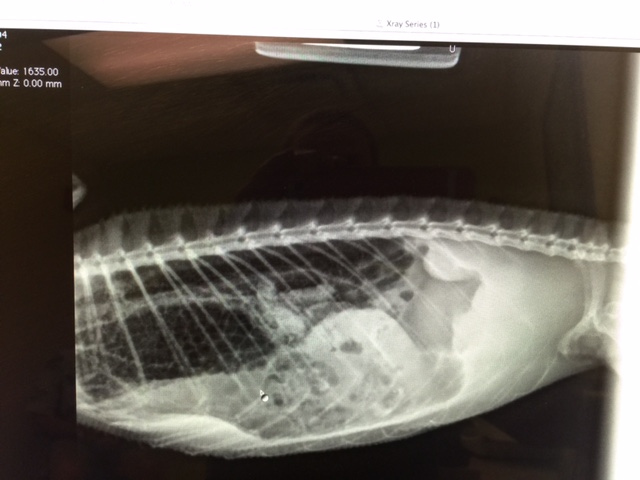

My girl that was receptive, Fiona has been having a hard time laying a small clutch of eggs. I took her to the vet last Thursday the 17th and he did an x-ray. It's the first x-ray below. You could only see 6 or 7 eggs and the vet said they didn't seem calcified. All day this past Wednesday she tried to lay. She stayed butt first in a rather shallow hole all day Wednesday, all night Wednesday and she stayed in the hole most of the morning Thursday. Then she covered the holes and returned to her branch. I gave her a long mist and she ate for me. There was only one tiny egg on the top of the soil in the laying bin not even close to the hole. I sifted through the sand twice and no more eggs. I took her back to the vet this passed Thursday the 24th and he did another x-ray. You really couldn't see any eggs. He had me give her a drop of liquid calcium everyday and said that might help the eggs to calcify or she might absorb them or he might have to do surgery. Yesterday she was back in the laying bin again...all day and all night. At first with her head down digging and then head out like she's trying to lay. She laid two more small eggs in the hole this time. She is scheduled for surgery this Thursday at 8 am. Please keep my sweet girl in your thoughts and prayers.

My beautiful Fiona and her x-rays.